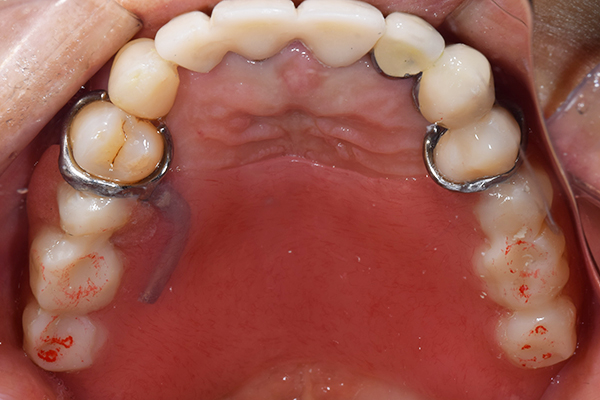

金属を使用して、薄く違和感が少ない入れ歯が完成しました。 また、見た目にも気を使い、バネが見えにくい様な構造にしました。

義歯は下顎で、しっかり噛めること、違和感の少ないものという希望があったため、なるべく入れ歯を薄く作成するために金属をしようした義歯とした。

また、見た目もあまり義歯が目立たない様に、バネの部分を見えにくいように作成した。

入れ歯は極力薄くするために金属を使用しました。しっかり噛める様にするため、ノンメタルクラスプデンチャーにはしませんでした。

入れ歯を入れた状態のお口の中の写真です。バネも極力目立たないように作成しています。

こちらが完成したかぶせ物と入れ歯です。かぶせ物にはアタッチメントをつけて金属のバネが見えない構造になっています。 入れ歯自体も金属を使用して、極力違和感がでないように、薄く作成しました。

お口の中に入れた状態です。 非常に見た目もよい出来となりました。 バネがみえないと見栄えが全然ちがいます。